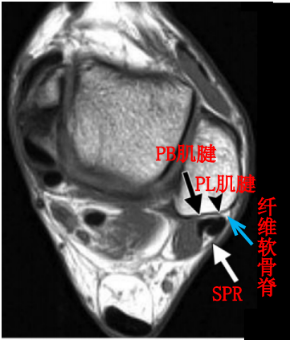

纤维软骨脊(FCR):腓骨外踝窝的外侧缘有一纤维软骨形成的缘,构成了窝的结构。该纤维软骨脊近端明显,向远端渐变小,使得沟的整体深度增加了2-4mm,且形状更适于容纳腓骨肌腱,从而促进应力分散。

腓骨上支持带(SPR):起于腓骨外侧面和腓骨外踝窝,绕过腓骨肌腱后止于跟骨和跟腱外侧。SPR没有直接牢固固定于纤维软骨脊,而是与腓骨外侧面的骨膜融合。

MRI:能更清楚地显示软组织损伤情况,如支持带撕裂和腓骨肌腱半脱位。对于指导临床治疗及后期随访观察疗效具有重要参考价值。